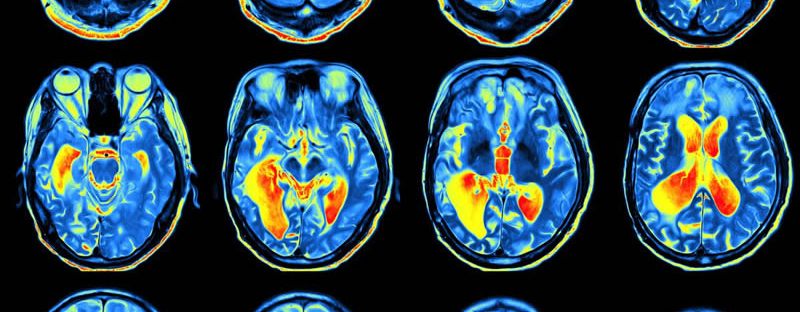

One of the primary functions of sleep is to facilitate physical and mental restoration. During the waking hours, the brain accumulates metabolic waste products that can be detrimental to its proper functioning. Studies [1] have shown that during sleep, the glymphatic system becomes highly active, clearing away toxins and waste products that accumulate in the brain throughout the day. This process promotes cellular repair, ensuring that the brain is in optimal condition for the next day’s activities.